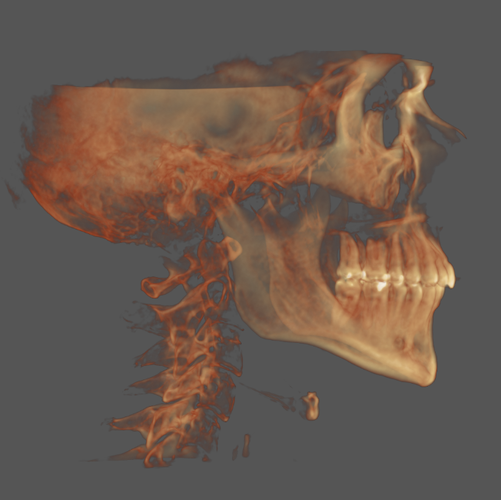

Planning on SARPE soon, too old for most ORTHO to work unfortunately.

Obviously leaning out which i am in the progress of but other than that not sure what else I can do or what my weakest features are. (My mandible is obviously recessed as is my maxilla.)